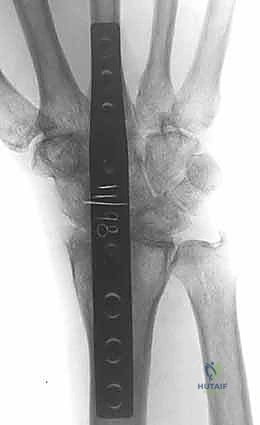

5. التثبيت بالشريحة والمسامير (Plate Fixation)

يتم استخدام شريحة معدنية خاصة (Wrist Fusion Plate)، غالباً مصنوعة من التيتانيوم، مصممة خصيصاً لتناسب تشريح الرسغ. يتم تثبيت هذه الشريحة بمسامير قوية تمتد من عظم الكعبرة في الساعد، مروراً بعظام الرسغ، وصولاً إلى العظم المشطي الثالث (Third Metacarpal) في اليد. هذا التثبيت الصلب يمنع أي حركة ويسمح للعظام بالالتحام لتكوين كتلة واحدة صلبة.

6. الإغلاق (Closure)

بعد التأكد من قوة التثبيت باستخدام جهاز الأشعة السينية داخل غرفة العمليات (C-arm)، يتم إعادة الأوتار إلى مكانها، وإغلاق الشق الجراحي بغرز تجميلية دقيقة لتقليل الندبات، ثم يتم وضع اليد في جبيرة أو دعامة صلبة لحمايتها.